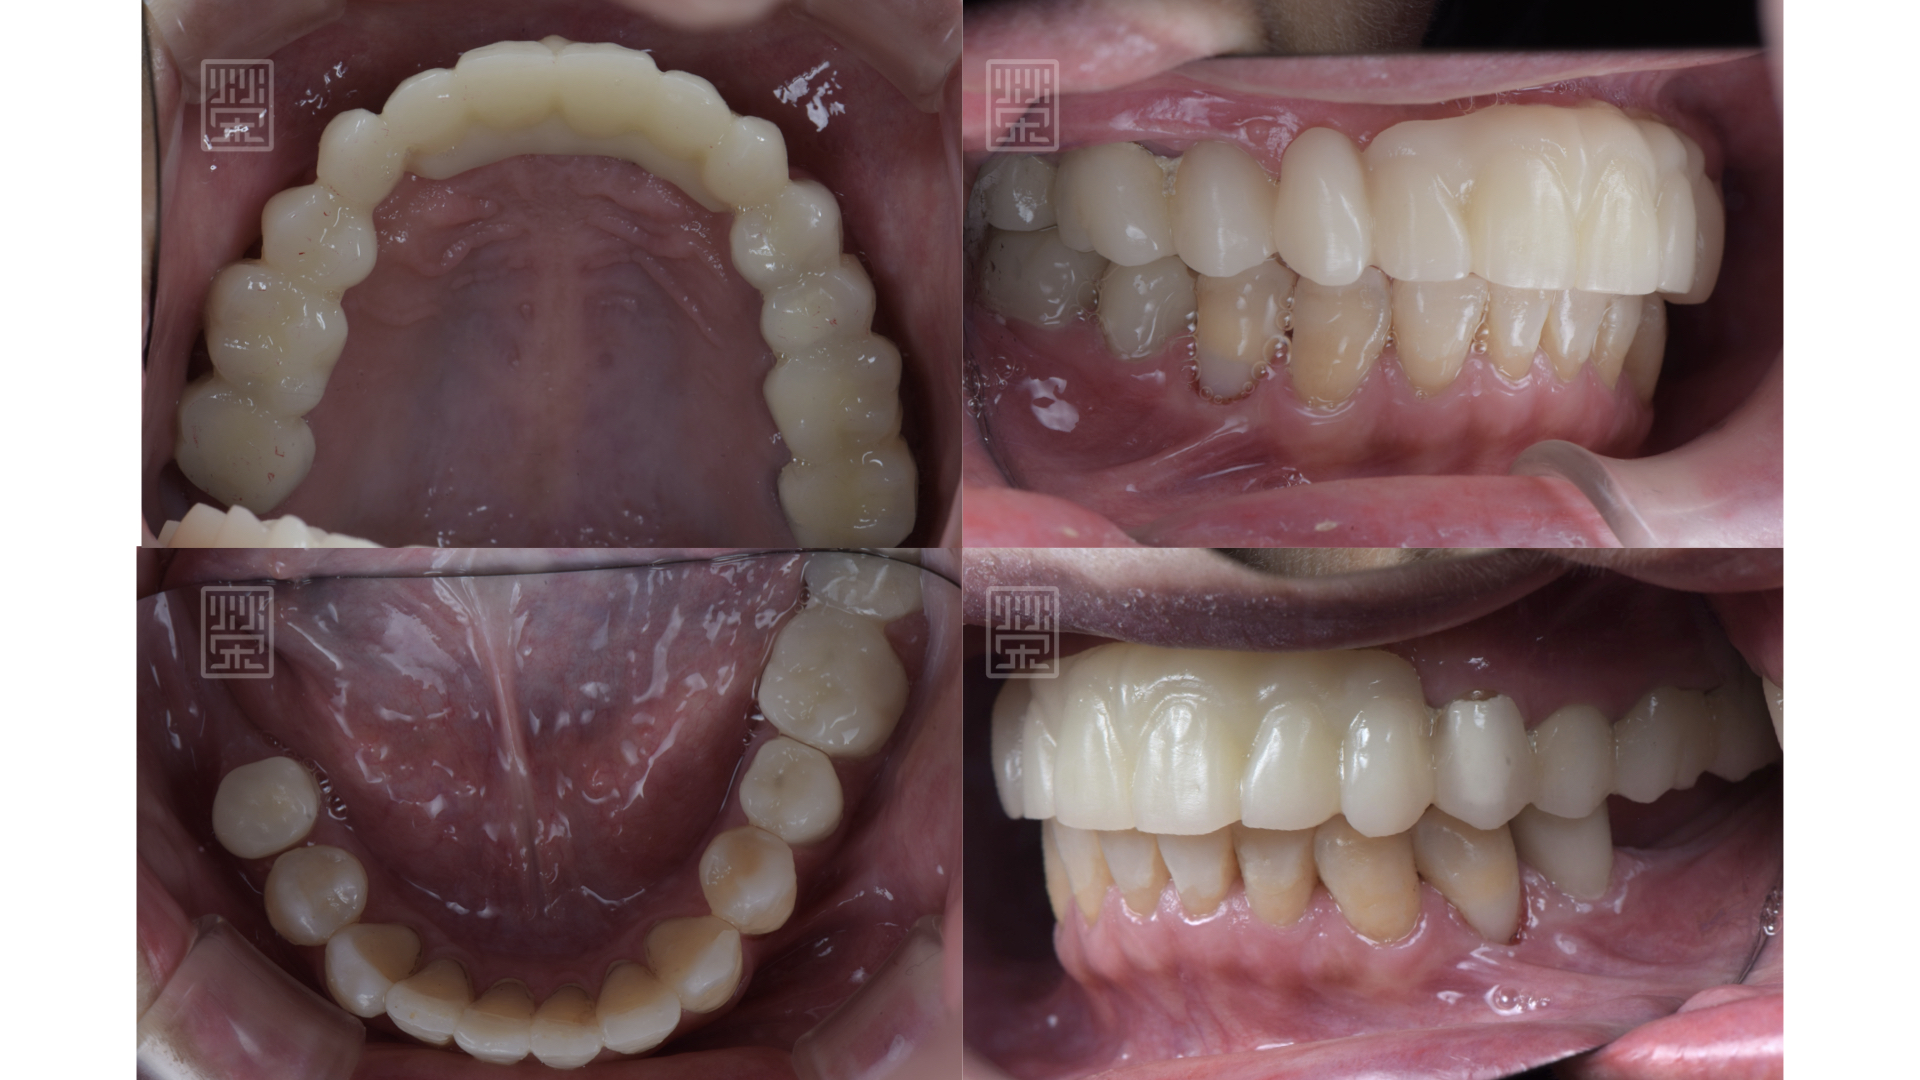

用全瓷牙橋與牙齦色陶瓷,恢復牙齒外觀與型態

玻璃陶瓷貼片改變下顎門齒顏色與型態

全瓷贋復物完成

適當的咬合分配

藉由臨時假牙、矯正、更新臨時假牙,讓型態、長度、唇形充分瞭解與溝通

自信開朗的笑容